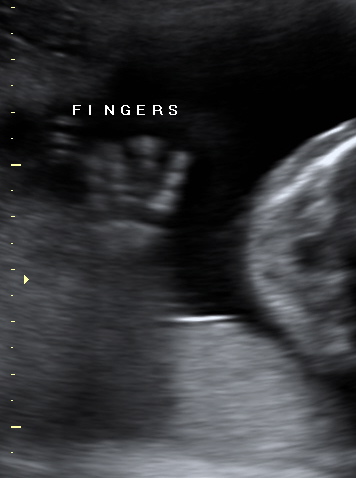

We were also lucky enough to receive around 20 scans, all of various parts of the twins. Here is my favourite (I have been telling everyone this is one of the twins waving hi!)